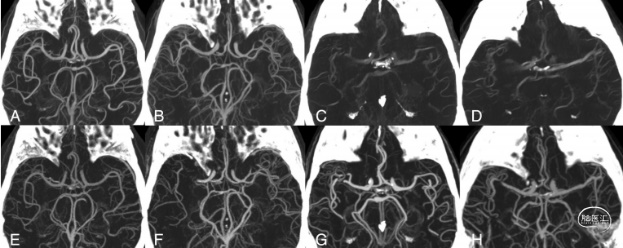

图2. DL-CBCTA 70 kev图像(上)和CTA(下),MIP切片厚度为35mm。A-B. 质量可接受的DL-CBCTA扫描。C-D. 受运动伪影影响的数据集中的典型扫描。下一行(E-H)为相应的CTA。F、G和H显示右侧MCA闭塞,在DL-CBCTA成像时已被解决。本研究仅评估了未受影响半球的动脉解剖。